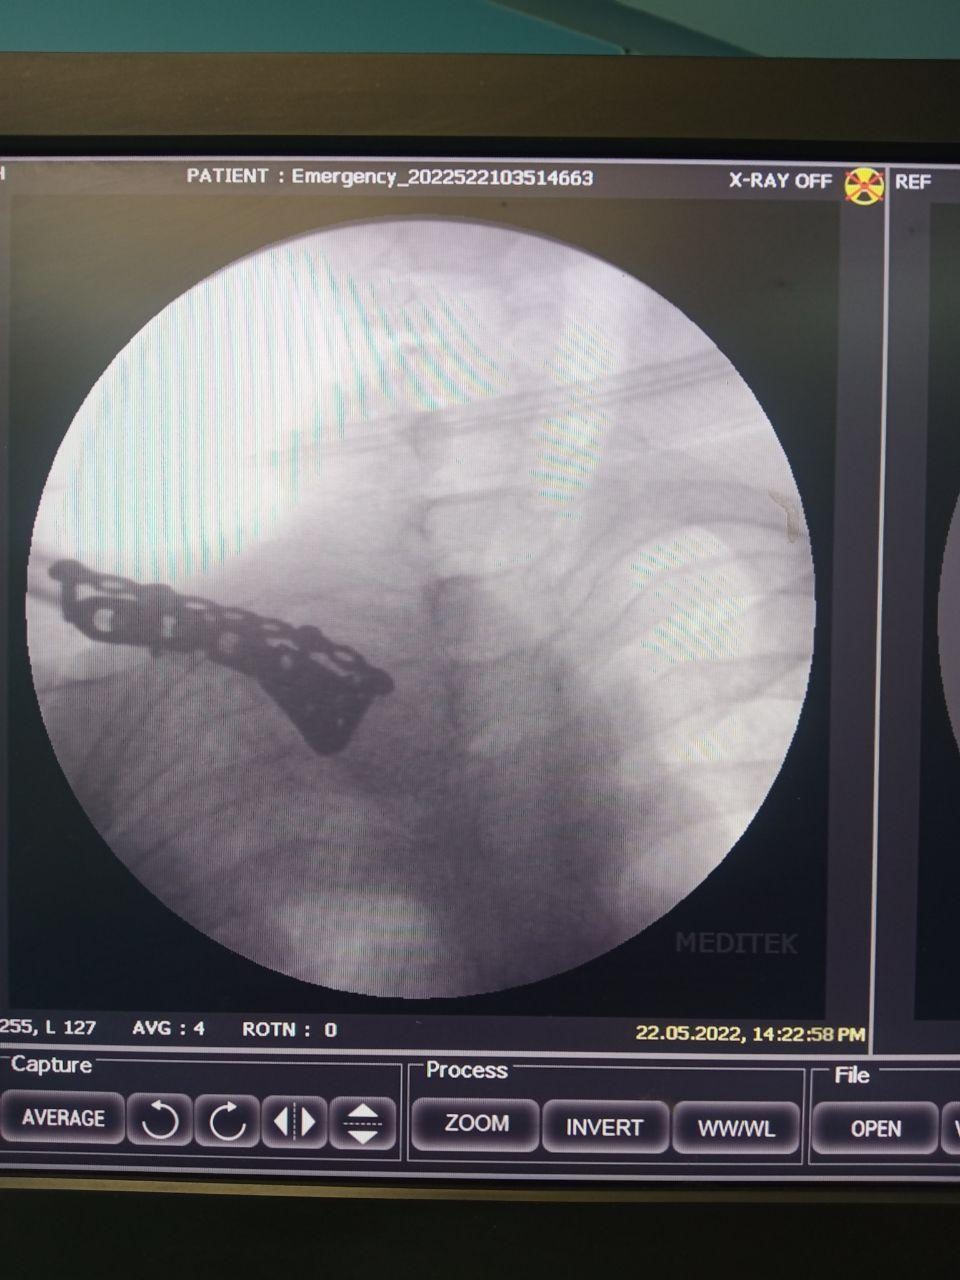

Surgical management of the non-union with an ORIF was performed under interscalene block with sedation. In a semi-sitting position, the non-union site was opened using a 10-cm longitudinal incision at the SC joint. The fracture site was exposed, edges curated, and hypertrophic callous was removed from the lateral sharp overriding edge (Fig. 3a), both edges have bleeding bone, approximated fixed by using left-sided lateral end clavicle locking plate (usually lateral portion could fit on the clavicle medial end) anteriorly with 4, 2.7 mm locking screw in medial fragment and 3, 3.5 mm cortical locking screw in the lateral fragment (Fig. 3b). Intraoperatively we found the purchase of 2 screws in the medial fragment unstable. Hence, we have augmented the fixation with a 3.5 mm recon plate superiorly with two simple screws in the medial fragment and two simple screws in the lateral fragment (Fig. 3c). A stable fixation was obtained without bridging the SC joint. The c-arm image is attached (Fig. 4).

Figure 4: Intraoperative fluoroscopy (C-arm) image confirming stable fixation with dual plating.